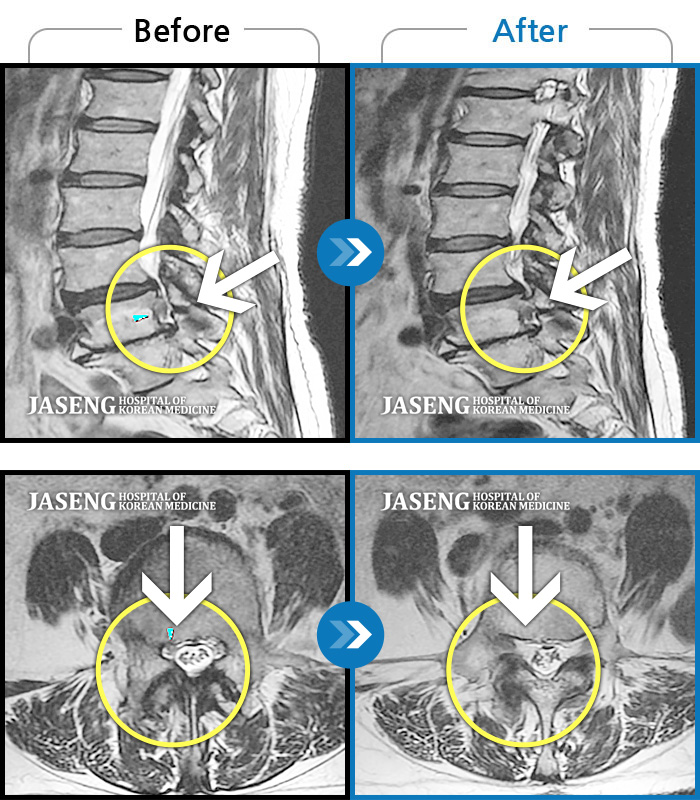

허리디스크

보라매 · 왕오호 원장

좌측 허리 통증과 좌측 다리 저림

촬영시기

2017.08.26 ~ 2018.08.21

2018.12.28

조회수 190